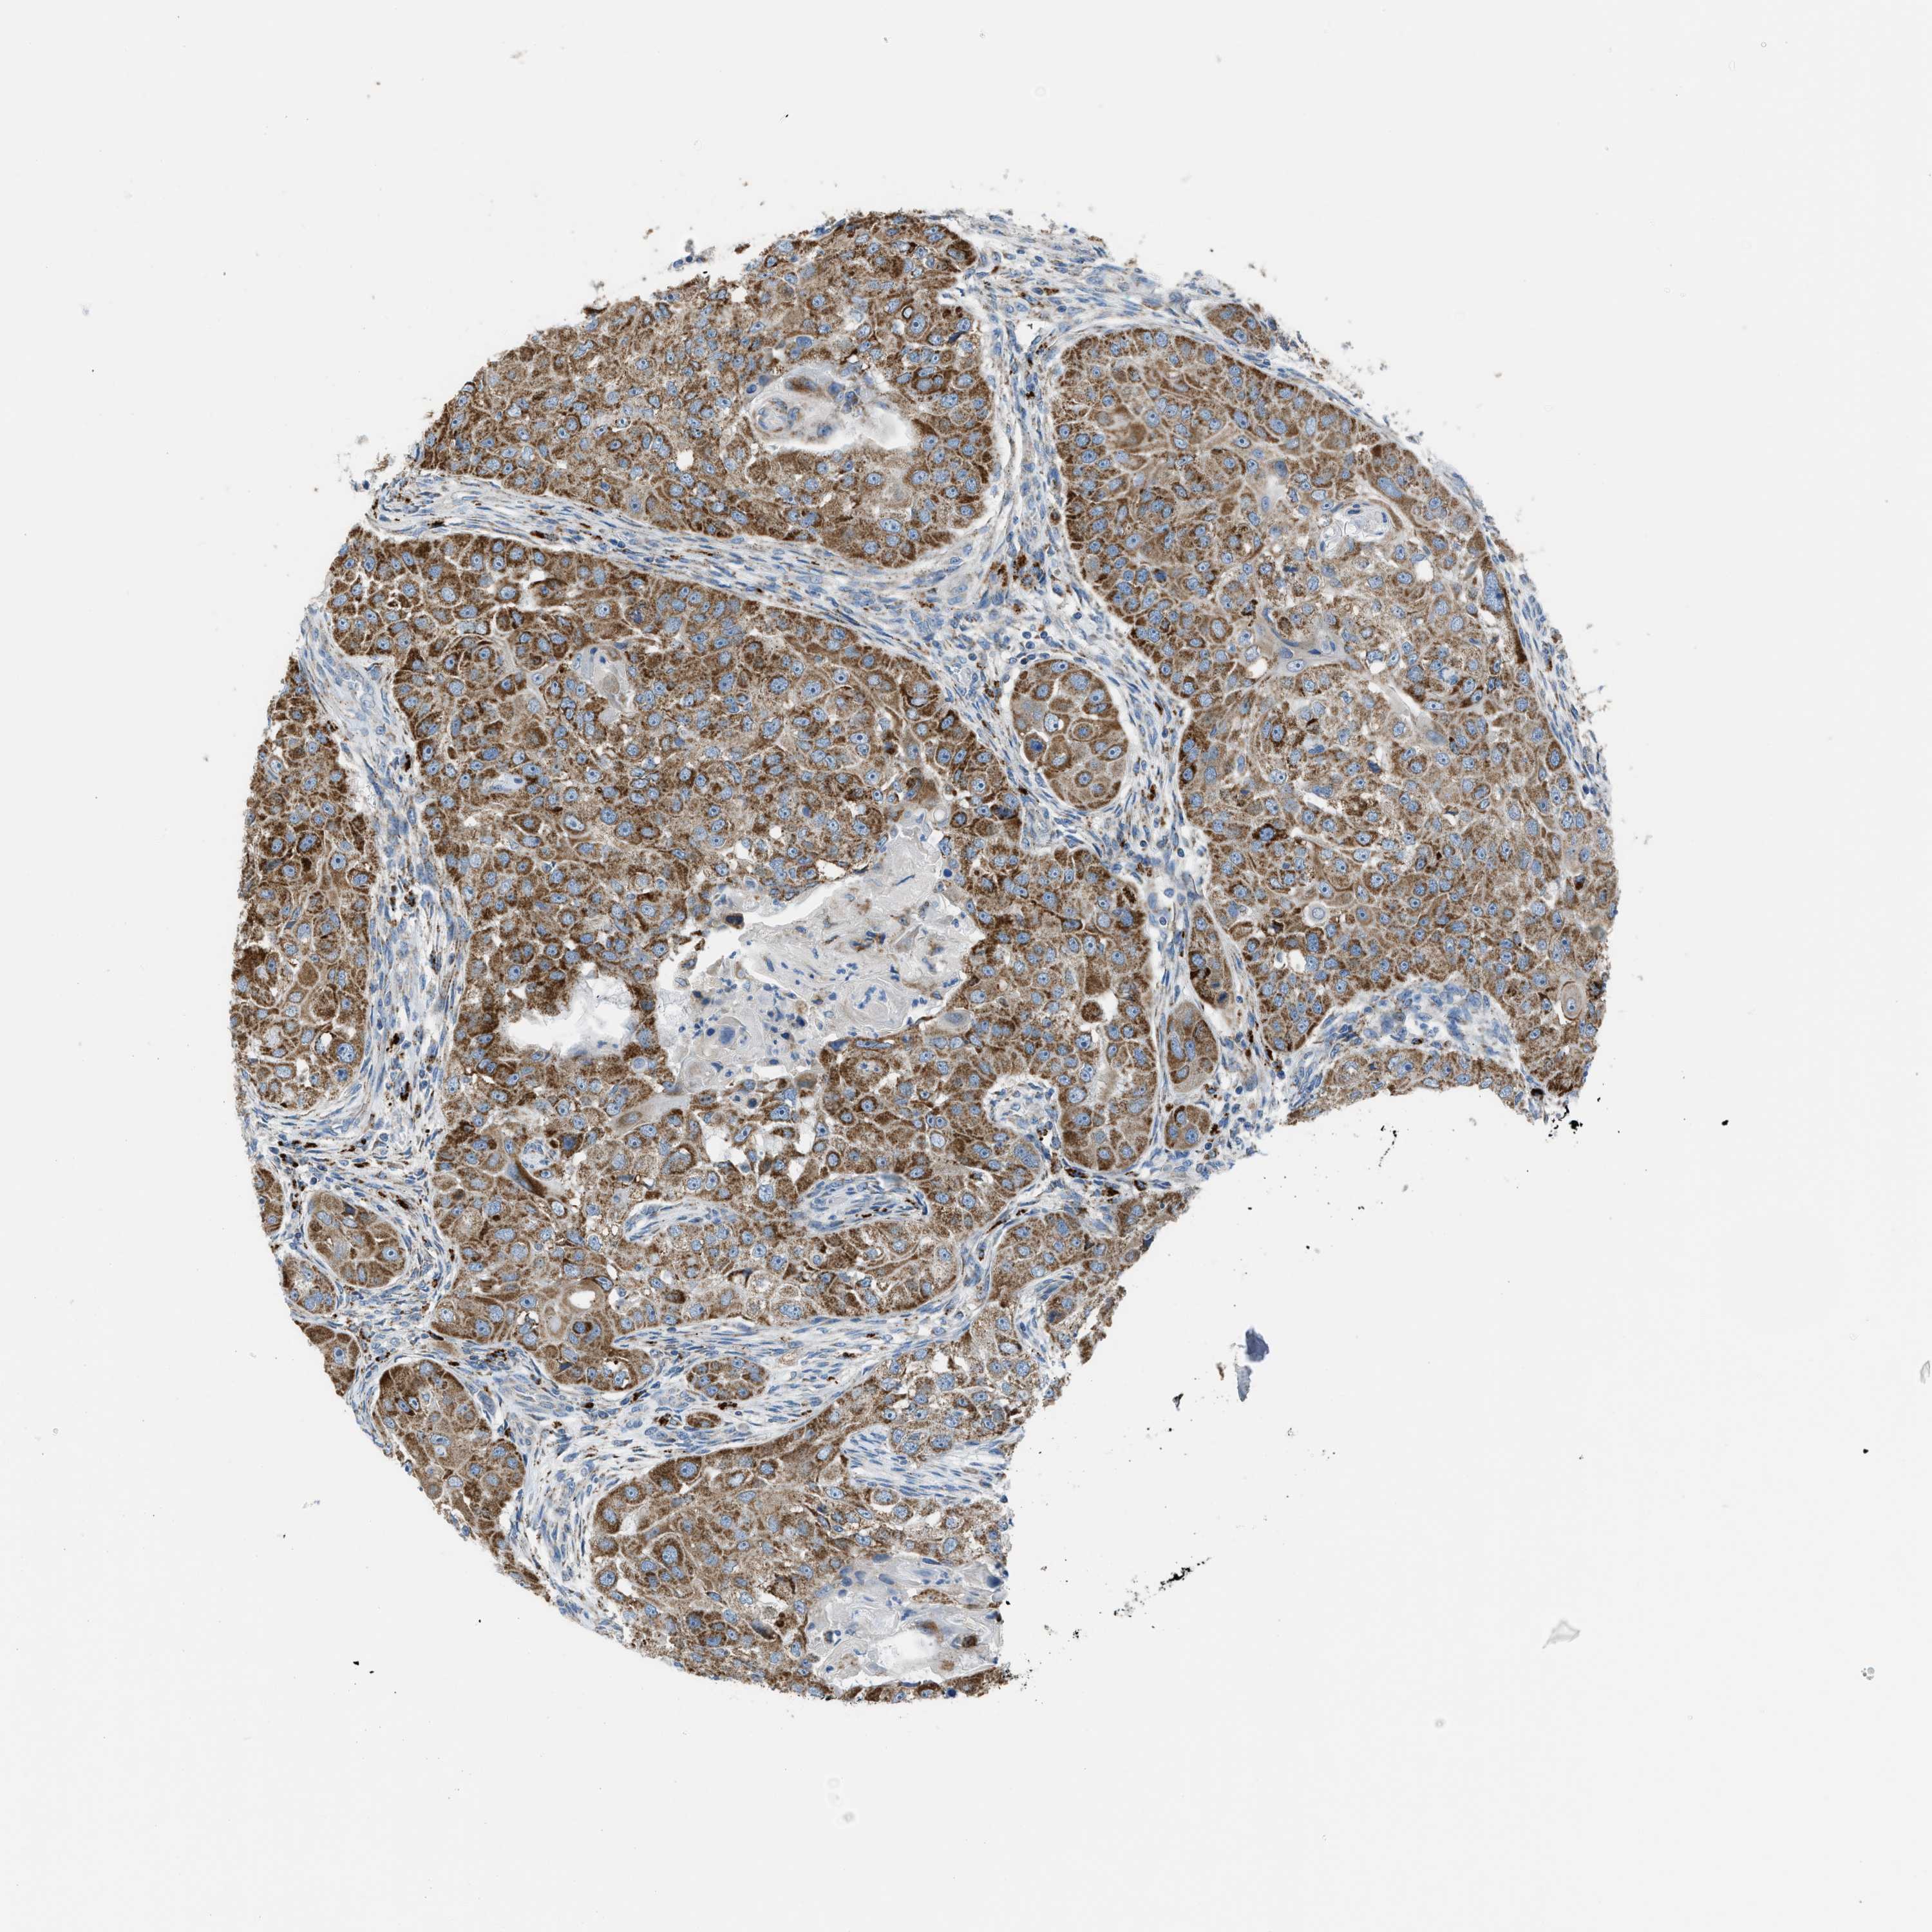

HEAD AND NECK CANCER - Protein expressioni

A mouse-over function shows sample information and annotation data. Click on an image to view it in a full screen mode. Samples can be filtered based on level of antibody staining by selecting one or several of the following categories: high, medium, low and not detected. The assay and annotation is described here.

Antibody stainingi

Antibody staining in the annotated cell types in the current human tissue is reported as not detected, low, medium, or high, based on conventional immunohistochemistry profiling in selected tissues. This score is based on the combination of the staining intensity and fraction of stained cells.

Each image is clickable and will lead to virtual microscopy that enables deeper exploration of all samples and also displays staining intensity scores, fraction scores and subcellular localization as well as patient and tissue information for each sample.

Antibody HPA016552

Staining

High

Medium

Low

Not detected

Intensity

Strong

Moderate

Weak

Negative

Quantity

>75%

75%-25%

<25%

None

Location

Nuclear

Cytoplasmic/membranous

Cytoplasmic/membranous,nuclear

Squamous cell carcinoma, NOS